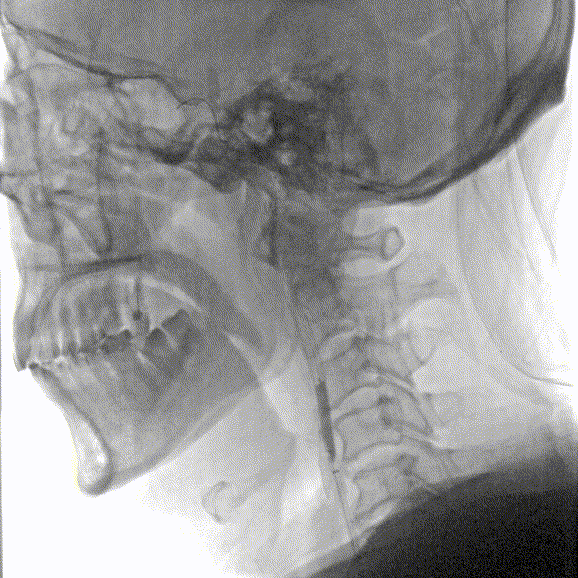

影像信息

主动脉弓上血管多发斑块形成。

左侧锁骨下动脉显示左侧椎动脉开口重度狭窄,狭窄率85%,供血至PICA。

双侧颈动脉造影提示双侧颈内动脉多发斑块形成,远端血管显影良好。

右侧锁骨下动脉造影提示右侧椎动脉主供血,开口无狭窄,椎动脉V4段局限性重度狭窄,狭窄率 80%,远端基底动脉及分支血管显影良好。

常规消毒、铺巾后,采用改良Seldinger技术穿刺右桡动脉。造影导丝和Sim2造影导管将7F EasyRadial™输送导管置于椎动脉。

正侧位造影提示右侧椎动脉重度狭窄。